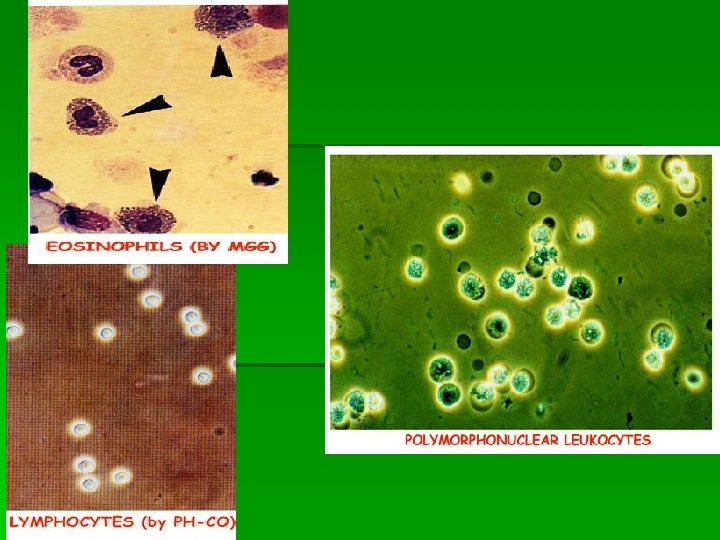

Лейкоцитурия –>2000 лейкоцитов в 1 мл мочи. Лейкоцитарная формула мочи (в норме ~ нейтрофилы – 80 %, лимфоциты – 20 %) Лимфоциты > 20% Нейтрофилы 90 -100% Макрофаги Эозинофилы 5 -60% -активный волчаночный нефрит - подострый ГН -обострение ХГН -нефротический синдром при амилоидозе -интерстициальный нефрит -отторжение трансплантата Инфекция мочевых путей Амилоидоз -лекарственный нефрит -интерстициальный нефрит -быстропрогрессирующий ГН -Ig A- нефропатия